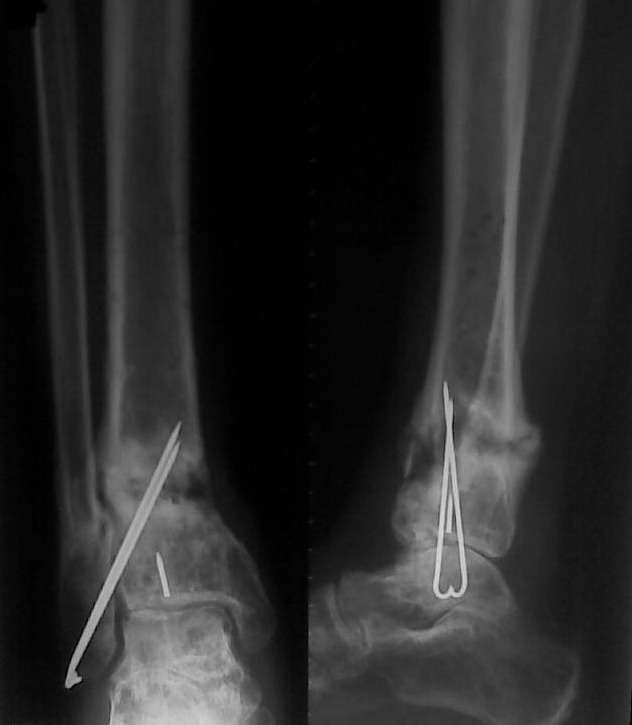

Уважаемые коллеги, обратилась больная 30 года, травма 1 год назад, открытый перелом дистального метаэпифиза левой голени, закрытый перелом левой таранной кости, закрытый перелом наружной лодыжки слева. Больная была прооперирована в солидном лечебном учреждении был произведен остеосинтез переломов (снимков пока нет). Послеоперационный период осложнился нагноением, конструкции были удалены. На сегодняшний день имеется следующее: по переднее-медиальной поверхности имеется свищ около 5 мм в диаметре с небольшим количеством гнойного отделяемого, конечность опорна, боли при нагрузке практически нет. Нервно - сосудистый статус без патологии. Подошвенное сгибание 10, тыльное 8 градусов. Снимки представлены ниже. Как лучше поступить в данном случае? имеется 2 варианта: 1. Удалить спицы, качественная секвестрнекрэктомия, лаваж полости с последующим заполнением её цементными бусами с антибиотиком. С целью профилактики перелома наложить простейший АВФ из двух колец. Через 2-4 недели (при благоприятном течении процесса) удалить бусы и заполнить полость аутографтом. Что смущает при этом варианте: малый размер полости 20 х 30 мм - мало цемента с антибиотиком - недостаточная концентрация антибиотика. Кроме того, дефект расположен вблизи сустава, где существует малое количество мягких тканей. Смущает так же состояние таранной кости. 2. Выполнить резекцию очага с последующим замещением дефекта по Илизарову. Больная и родственники не совсем в восторге от этого варианта (длительные сроки, неудобства, связанные с ношением АВФ). Хотя возможно это и лучший вариант. Про таран уже говорилось выше. Какие ещё возможны варианты ? С уважением Д.Б.

Таран выглядит вполне оптимистично.

Добрый день. Я не вижу особых проблем с тараном. По крайней мере на Рснимках. Можно сделать КТ голеностопа и посмотреть таран прицельно. Родственникам объяснить (к слову о том что они не в восторге от предложенного - варианта лечения), что пусть скажут спасибо что вы взялись за работу с таким г... (а метаться надо бы раньше, в том числе и материально). Если гноя откровенного нет, то удалить спицы, взять посев из раны на чувствительность, пролечить антибиотиками с учетом посева а дальше 2 варианта или рискнуть на экономную секвестрнекрэктомию с одновременным заполнением дефекта аутотрансплантатом и наложением метафизарной пластины или сделать резекцию концов большеберцовой кости, наложить аппарат и дать компрессию. Когда появятся признаки консолидации то удлинить конечность.

Как кажется, целесообразно сделать фистулографию, по результатом прокрасить зеленкой, экономно удалить раскрашенное; железо. Далее АВФ, "огонь дистракции" и тд. Если все закроется, то можно подумать о конверсии способа фиксации, например, на гвоздь. Если нет- повторная обработка с бусами. Таран скорее жив, чем мертв (субхондральная зона остеопороза).

У данного больного имеется неполное сращение, контролируемый краевой свищ и варус. Трудно закрыть пергаментную кожу вокруг свища и рубцовые изменения. Нечем прикрыть антибиотические бусы или пластину с медиальной стороны.